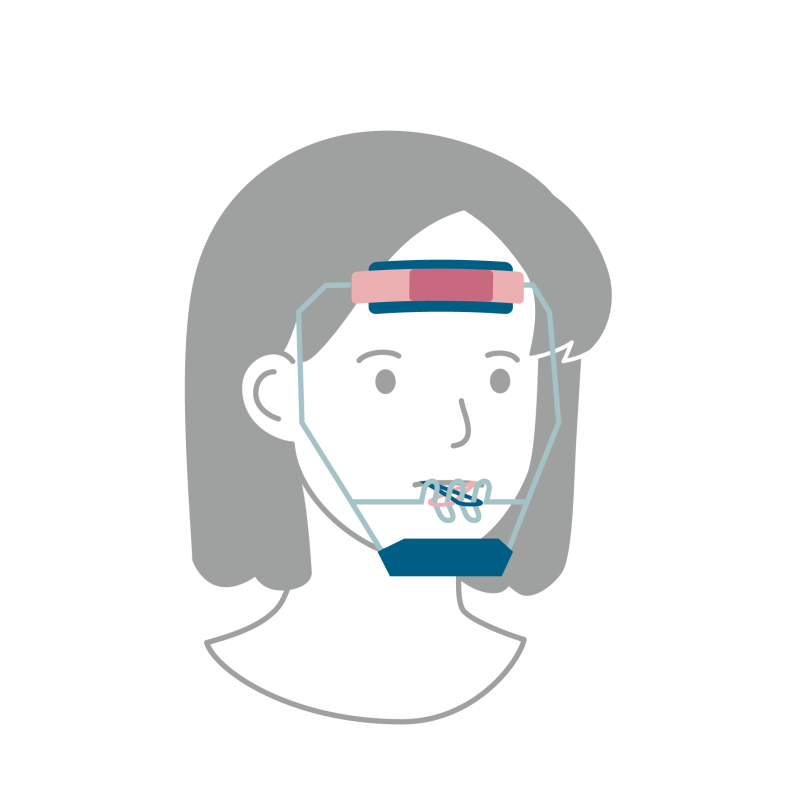

子どもの矯正治療は混合歯列期のこの時期からスタートします。部分的に矯正装置を装着し、混合歯列期の時点でみられる問題を解決していきます。この時期は、顎骨の成長コントロールを行うことができるため、上顎前突(じょうがくぜんとつ=出っ歯)や下顎前突・反対咬合(かがくぜんとつ=受け口)などの骨格性の異常に対する治療が大きな治療目標になることが多いです。この時期にある程度、骨格に対する治療や永久歯の並ぶすき間の確保などを行うことができると、二期治療・永久歯列期での治療の幅が広がります。

しかし、骨格性の異常(出っ歯や受け口)の程度が大きい場合、すでに成長のコントロールを行うことができない時期であるため、この問題を解決するためには手術を伴う外科的矯正治療が必要になることもあります。